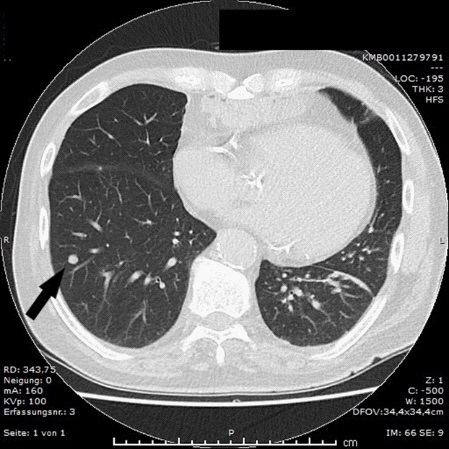

The nodule was revealed by the X-Ray examination because of the continuous cough and left chest pain. There were no dysphagia and any clinically significant laboratory changes. In anamnesis the oesophagocoloplasty for squamous cell carcinoma (SCC) of the oesophagus (pT2N1Mo) with adjuvant radio-chemotherapy was performed 10 years before. We performed videoassisted (VATS) wedge resection of the right lower lobe with the lesion. The pathology finding was colon type adenocarcinoma (Figure 2).

Figure 2: The photo of pathology of adenocarcinoma in the colon interposition (endoscopic biopsy).Blood tumour markers were normal (CEA 1,7 ng/ml, CA 19-9 9 U/l). Colonoscopy revealed no changes. By performing esophagogastroduodenoscopy (EGDS) we found a tumour stenosis in colon interportal (30 cm from incisor teeth, Figure 3).